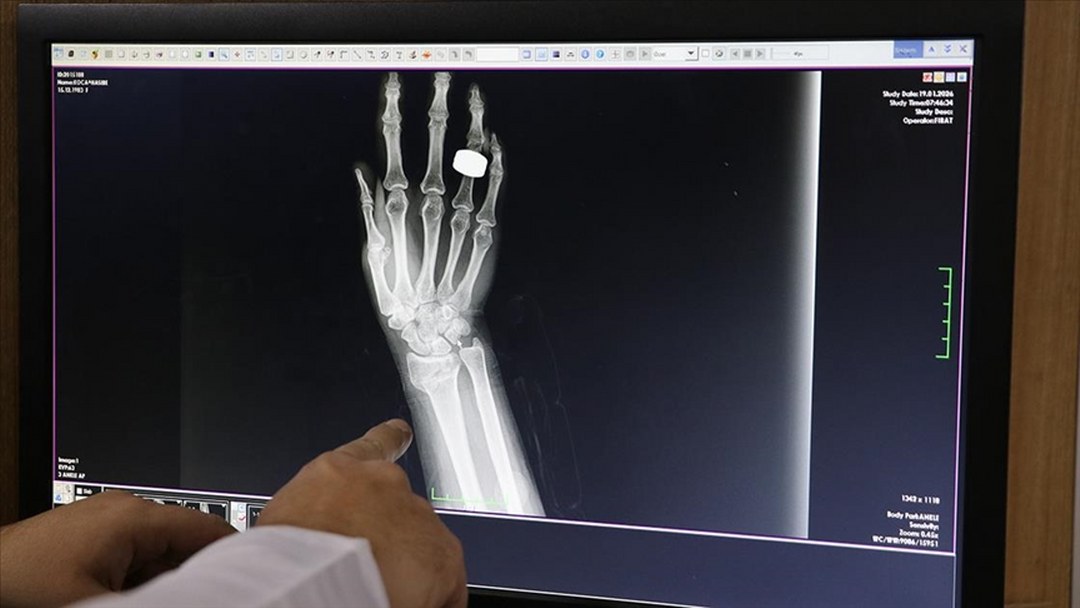

Kar yağışı ve ardından oluşan buzlanmanın düşme vakalarını artırdığını vurgulayan Gül, “Genellikle buzlu zeminde kayma ve araçların kayması sonucu meydana gelen trafik kazaları nedeniyle başvurular oluyor. Bu düşmeler sonucunda el ve ayak bileği kırıkları başta olmak üzere leğen kemiği, kuyruk sokumu ve omurga kırıkları da görülebiliyor.” dedi.

Düşerek yaralanan vatandaşlardan Fatma Öncel de yolda yürüdüğü sırada düştüğünü, bileğinde ağrı hissetmesi üzerine hastaneye başvurduğunu söyledi.

Öncel, “Tedbir amaçlı hastaneye geldim. Yapılan kontrollerde kırık olmadığı, yumuşak doku zedelenmesi olduğu söylendi. Bundan sonra daha dikkatli olacağım.” dedi.

Karlı ve buzlu yolda düşme sonucu ayağı kırılan Eren Ergin (15) de düşme sonucu sağ ayağında kırık oluştuğunu ve ameliyat olacağını söyledi.

Ergin, “Şırnak’ta yollarda kar ve buz var, herkes dikkat etsin, düşmesinler.” dedi.